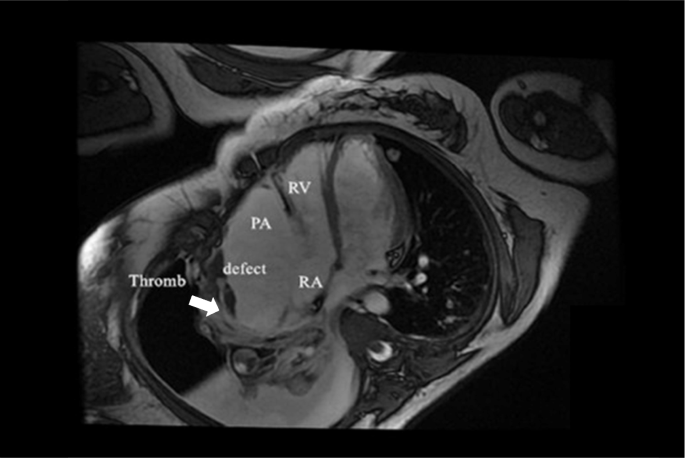

Three-dimensional transthoracic echocardiogram (TTE) showed an irregular cystic mass measuring 8.49*3.81 cm in the lateral wall of the right atrium, indistinctly demarcated from the pericardium. The mass obviously compressed the right atrium (Fig. 1). A contrast chest CT scan displayed a pseudoaneurysm with thrombosis inside the right atrium (Fig. 2). Multiple nodules in both lungs and on the right pleura, as well as right hydropneumothorax, were also noted. Contrast MRI demonstrated a 100 mm*48 mm pseudoaneurysm on the right side of the right atrium with a thrombus. There was a defect measuring 22.5 mm between the pseudoaneurysm and the right atrium (Fig. 3). PET-CT suggested that FDG metabolism inhomogeneity increased in the mass in the right atrium. FDG metabolism slightly increased in multiple nodules in both lungs. Multiple ground glass foci in both lungs were considered bleeding.

A 32-year-old woman was referred to our hospital for recurrent pericardial haemorrhagic effusion and pleural effusion. Three-dimensional transthoracic echocardiogram, contrast chest CT, and contrast MRI revealed a pseudoaneurysm on the right side of the right atrium with a thrombus. There was a defect between the pseudoaneurysm and the right atrium. PET-CT suggested that FDG metabolism inhomogeneity increased in the mass in the right atrium. Exfoliative cytology detection of massive pericardial effusion and pleural effusion revealed no tumour cells. Spindle cell sarcoma of the right atrium was not confirmed until the patient underwent right thoracic exploration and biopsy. Before a confirmed diagnosis, symptomatic treatment, such as chest effusion and pericardium effusion drainage, and transfusion of red blood cells were mainly used to relieve the patient’s symptoms. Unfortunately, the patient was lost to optimal treatments and passed away 20 days after the pathological diagnosis was made.